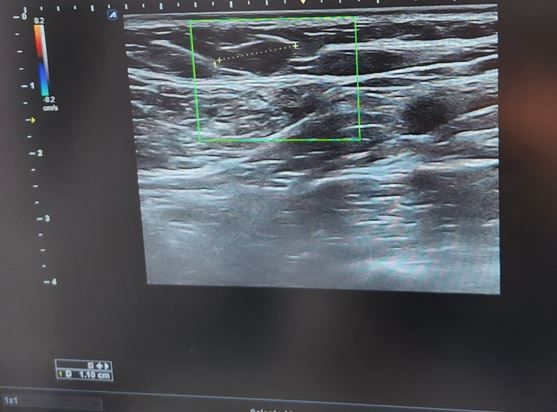

쇄골 위에 혹이 있어서 초음파를 했는데한번 봐주세요~

안녕하세요~ 3년전부터 쇄골 위에 구슬처럼 만져지는 혹이 있어 추적관찰중입니다~

1군데 병원에서는 제가 덩치도 있는 편이라 초음파에 보이는 저 부분이 지방층이다 지방층이 연결된거 보이지 않냐 라고 하시고

1군데에서는 임파선이라고 하시는데

참조해주신 영상의 경우 표시한 부분은 지방입니다

이 초음파를 기준으로 말씀드린다면 크게 걱정하지 않으셔도 됩니다

올려주신 사진상 지방으로 보입니다.